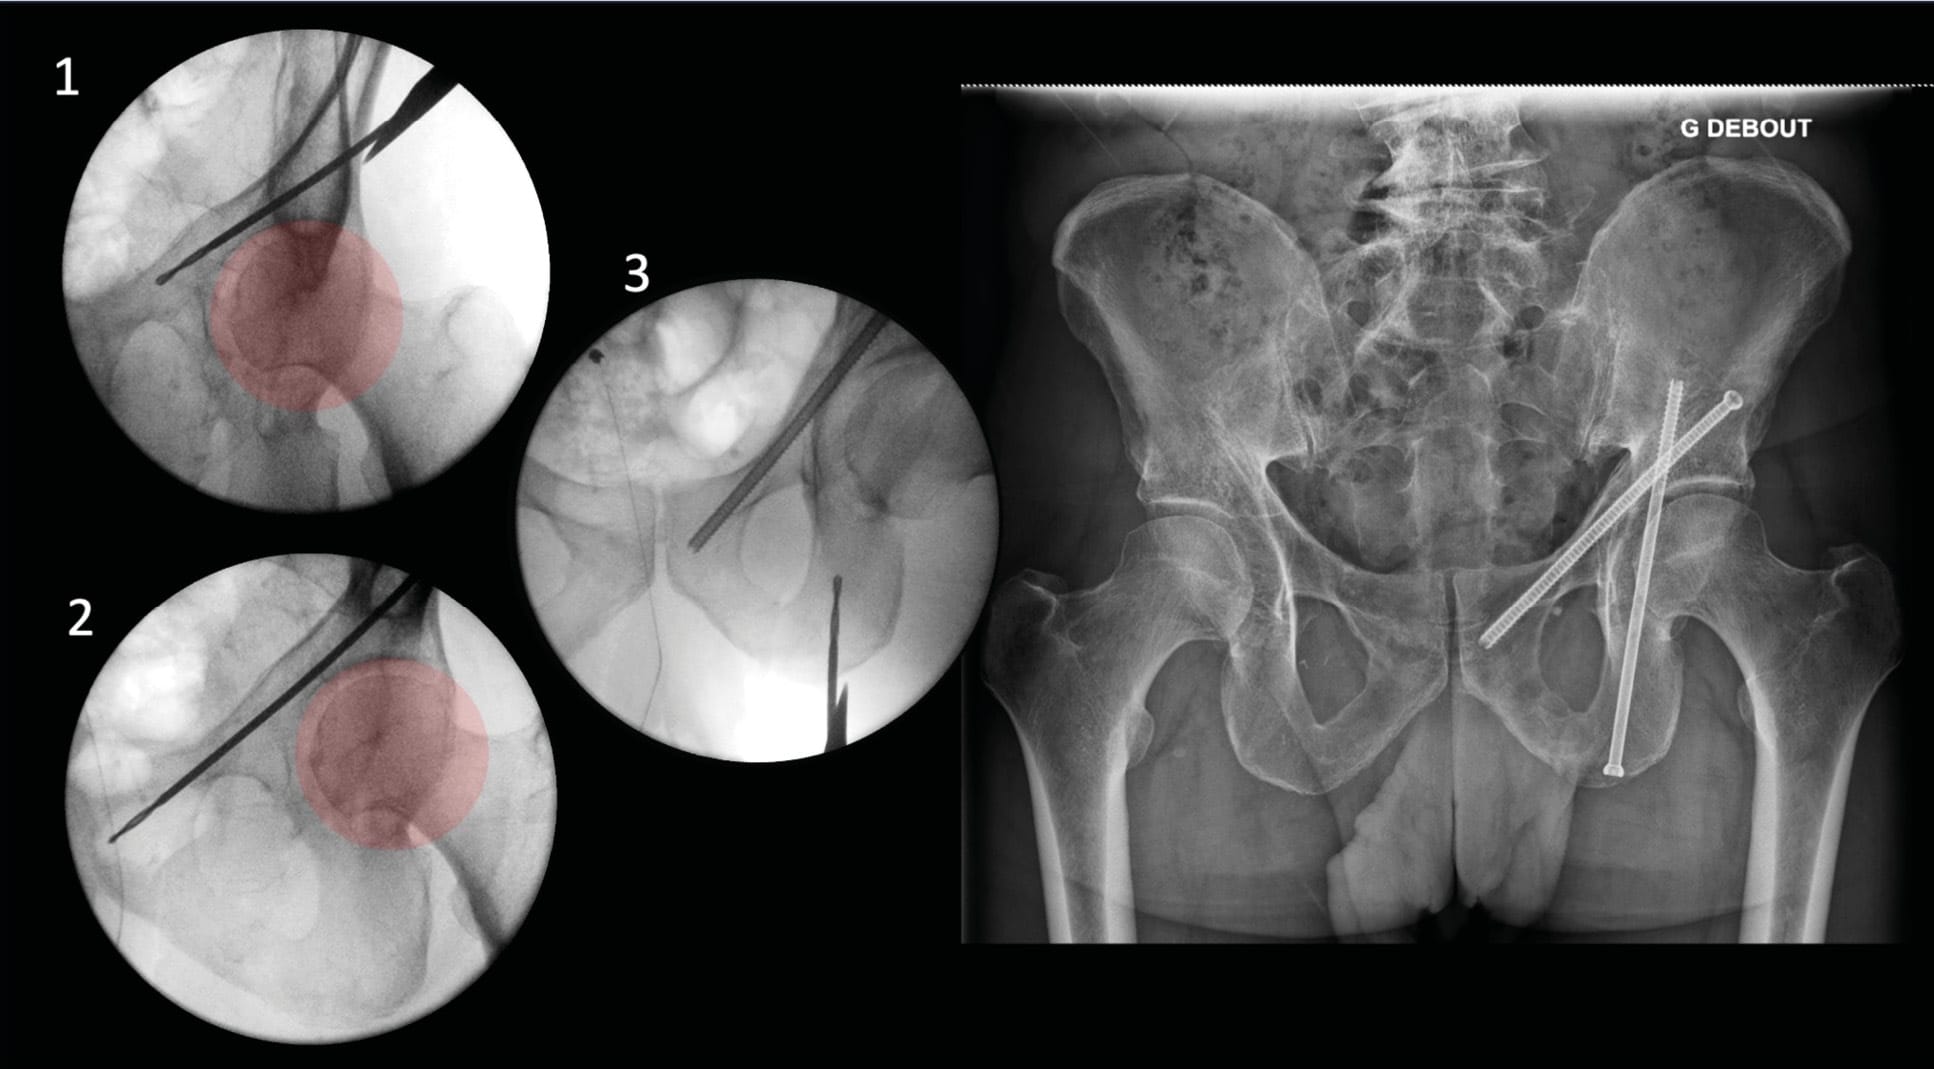

Anterior Column (AC) screw fixation

First described by Routt et al. in 1994, the use of intramedullary screws in the iliopubic ramus has demonstrated equivalence to plate fixation and superiority over non-operative treatment or external fixation. This technique is indicated for obturator ring fractures in pelvic ring injuries and anterior column fractures in acetabular fractures. Positive outcomes have expanded surgical indications, particularly in geriatric patients, with benefits for pain management and recovery of autonomy (Figure 9). This fixation can be performed either antegrade (from the gluteus medius pillar to the symphysis) or retrograde (reverse direction). The choice between these two techniques is not clearly established. However, for fractures closer to the symphysis (Nakatani I and II), retrograde fixation appears to offer an easier trajectory. Conversely, for lesions near the acetabulum, antegrade fixation seems more appropriate. The anatomy of the iliopubic ramus is highly variable, and certain corridors can be difficult to locate, even with reduced fractures. For fixation in cases of osteoporosis or early weight-bearing, bicortical purchase is recommended, particularly in the dense region of the acetabular roof [17] Tucker NJ, Stacey S, Kim YJ, DeLeon J, Richard R, Heare A, et al. Variables Associated With Loss of Fixation of Retrograde Rami Screws in Minimally Displaced Lateral Compression Type 1 Pelvic Ring Injuries. J Orthop Trauma 2024;38:215–9. https://doi.org/10.1097/BOT.0000000000002756.. The procedure is preferably performed in supine position, with a sacral cushion to avoid interference with the operating table. However, it can be performed prone when acetabular fracture requires posterior fixation. Surgical draping should extend to the edge of the table for the buttock and to the base of the penis or clitoris for the superior portion. The image intensifier is positioned facing the surgeon. For imaging views, the Outlet + three-quarter obturator view provides a "front view" of the obturator frame, thus guiding the trajectory in the cranio-caudal plane and allowing visualization of the entry point while monitoring for intra-articular hip penetration (Figures 3, 9, 10, 11). The orthogonal view, an Inlet view, helps manage trajectory convergence, avoiding medial neurovascular and uro-visceral structures. (Figure 3) For antegrade AC screw fixation, the skin incision is typically made halfway between the greater trochanter and the pillar bulge on the iliac crest, approximately 6 cm posterior to the anterior superior iliac spine. In obese patients, the incision should be placed even closer to the iliac crest. The bone entry point is located in the gluteus medius pillar, typically 2-3 cm above the hip joint, identified using fluoroscopy (Figure 10). For retrograde fixation, the entry point can be at the homolateral rectus tubercle, or even contralateral in very medial fractures (Figure 11). It can also be lateral to the symphyseal meniscus depending on the case. This technique makes hip joint passage more challenging. Once reduction is achieved if necessary, the guide wire can be advanced through the corridor manually using a T-handle; this method helps limit misplacements by allowing the wire to work and flex along the cortical walls of the corridor. When bone density is high, power tool use may be necessary. Once the wire position in the corridor is confirmed, a 6.5- or 7.3-mm screw is typically used, with partial or full threading depending on the fracture pattern and proximity to the joint.

One of the main complications is injury to the external iliac vessels or femoral nerve, located at the superior portion of the branch. A breach at this level may also go unnoticed if the outlet view is insufficient (Figure 12). The structures at risk in antegrade CA screw fixation are the gluteal muscles and their neurovascular pedicles, although this is a theoretical complication since no injuries have been reported in the literature. For retrograde CA screw fixation, the major risk is urogenital and thus differs between sexes. In women, the body and glans of the clitoris are the main structures at risk. It should also be noted that there is significant sensory nerve innervation that could be injured by this procedure. In men, the spermatic cords and corpus cavernosum are the main structures at risk. The spermatic cords can be easily palpated and identified before the procedure. To limit potential injury to these structures, it is recommended to perform clinical mapping when possible and careful dissection while protecting the procedure using a dedicated cannula.

Certain anatomical features, such as the parabolic shape of the iliopubic branch or external genital and abdominal anatomy, complicate this procedure. Many authors have described techniques to facilitate screw insertion. Another difficulty may arise from fracture displacement itself, making the corridor inaccessible. Various percutaneous reduction maneuvers are then implemented, such as traction, using a reduction frame, joystick wire, pusher, or performing a small suprapubic approach. One of these techniques uses a Métaizeau nail as a guide wire. This device facilitates progression through the corridor, limits false passages thanks to its blunt tip, and allows catheterization of the displaced fragment using its curved end. This technique thus enables reduction.

Tips / Tricks: To incise at the optimal trajectory, we recommend, when beginning to gain experience, using a standard 2.0mm Kirschner wire through the skin to evaluate, under fluoroscopy, the ideal entry point and appropriate trajectory before making the scalpel incision. This approach helps avoid having to force through soft tissues in case of inadequate skin incision, which could complicate screw placement. In case of conflict with the contralateral thigh (extreme morphologies), one technique involves exploiting the creep (bending) of the guide wire. The radius of curvature thus generated allows for a trajectory that would be physically impossible to achieve with a straight wire (Figure 13). Using a curved wire or Metaizeau nail is an effective technique for finding the corridor when it is difficult or narrow (for example, to place the screw as far from the joint as possible), while limiting the risk of false passages [18] David G, Rony L, Moullac D, Letissier H, Di Francia R. The “Metaizeau trick” to facilitate medullary pubic ramus screw insertion: A technical note. Orthop Traumatol Surg Res OTSR 2024;110:103879. https://doi.org/10.1016/j.otsr.2024.103879.. Another technique involves using a cannulated drill bit at the entry point, then inserting a pre-curved Kirschner wire. The progression of the wire, followed by the drill bit, is performed repeatedly inside the corridor (Figure 14).